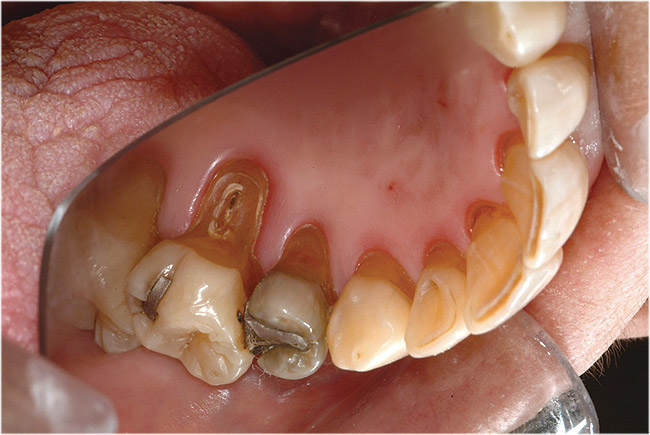

Figure  6  Erosion and abrasion in a xerostomic patient with Sjögren’s syndrome.

Figure 6